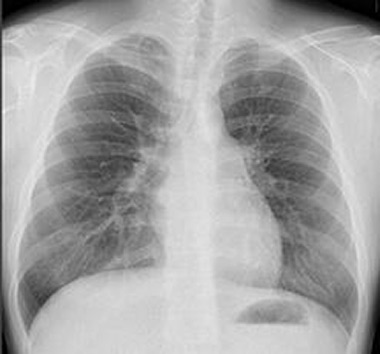

一般撮影装置

一般撮影とはいわゆる

レントゲン検査のことで、

主に胸部や腹部、

整形領域など全身の検査、

歯科領域や顎関節の撮影にも

使用されています。

従来ではフィルムでの撮影が主流でしたが、現在ではFPD(フラットパネルディテクタ)を使用しており、画像がデジタル化されたことによって撮影した画像を瞬時に確認することができ、現像する時間が無いため、非常に撮影効率が高くなっています。また画質の向上に伴い低線量での撮影ができるため被曝低減が可能となっています。